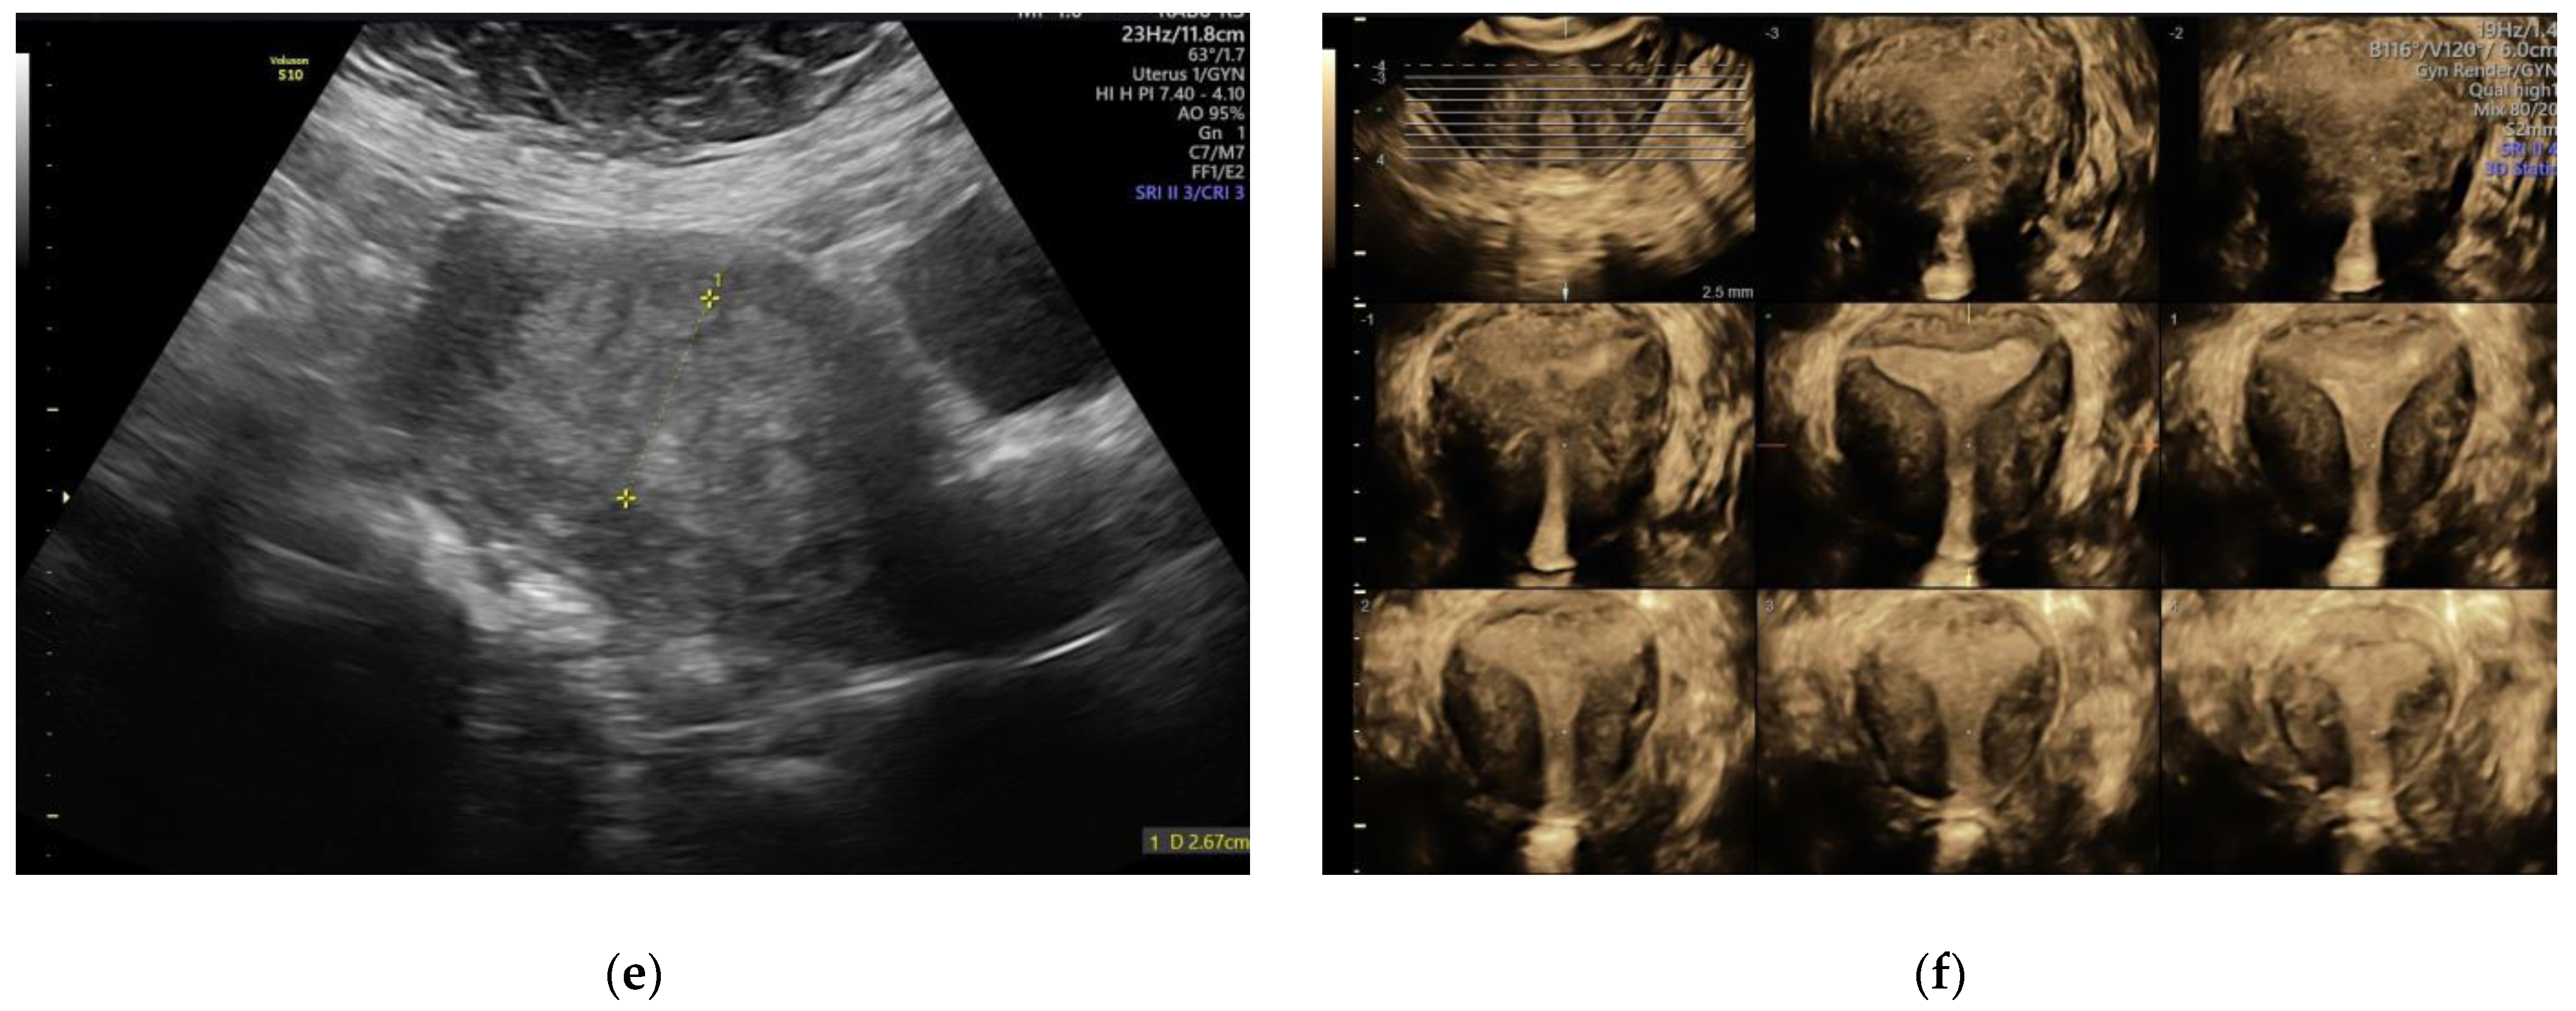

2.3. IETA Characteristics in Endometrial Pathology

3.2. IETA Ultrasound Criteria